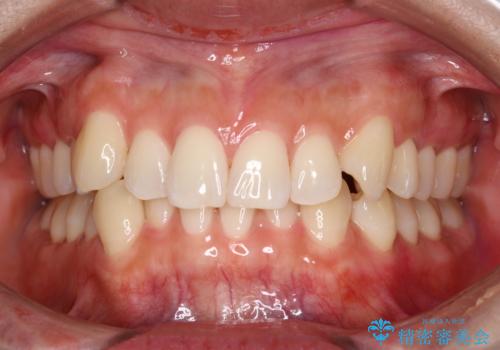

染め出しをしてエアフローで綺麗にクリーニング

染め出しを行い、歯みがき指導とエアフロー60分コースを行いました。

エアフローワンは、特殊なパウダーを混ぜた水を水面にジェット噴射することでバイオフィルム(プラーク)・ステイン(着色)・早期歯石を天然歯やインプラント周囲から除去することが可能な歯面清掃器具です。

従来の荒い研磨剤などを用いた歯面への負担が大きいクリーニングとは異なり、歯質の負担を最小限にした歯面清掃と歯周ポケット内のメンテナンスを行えます。